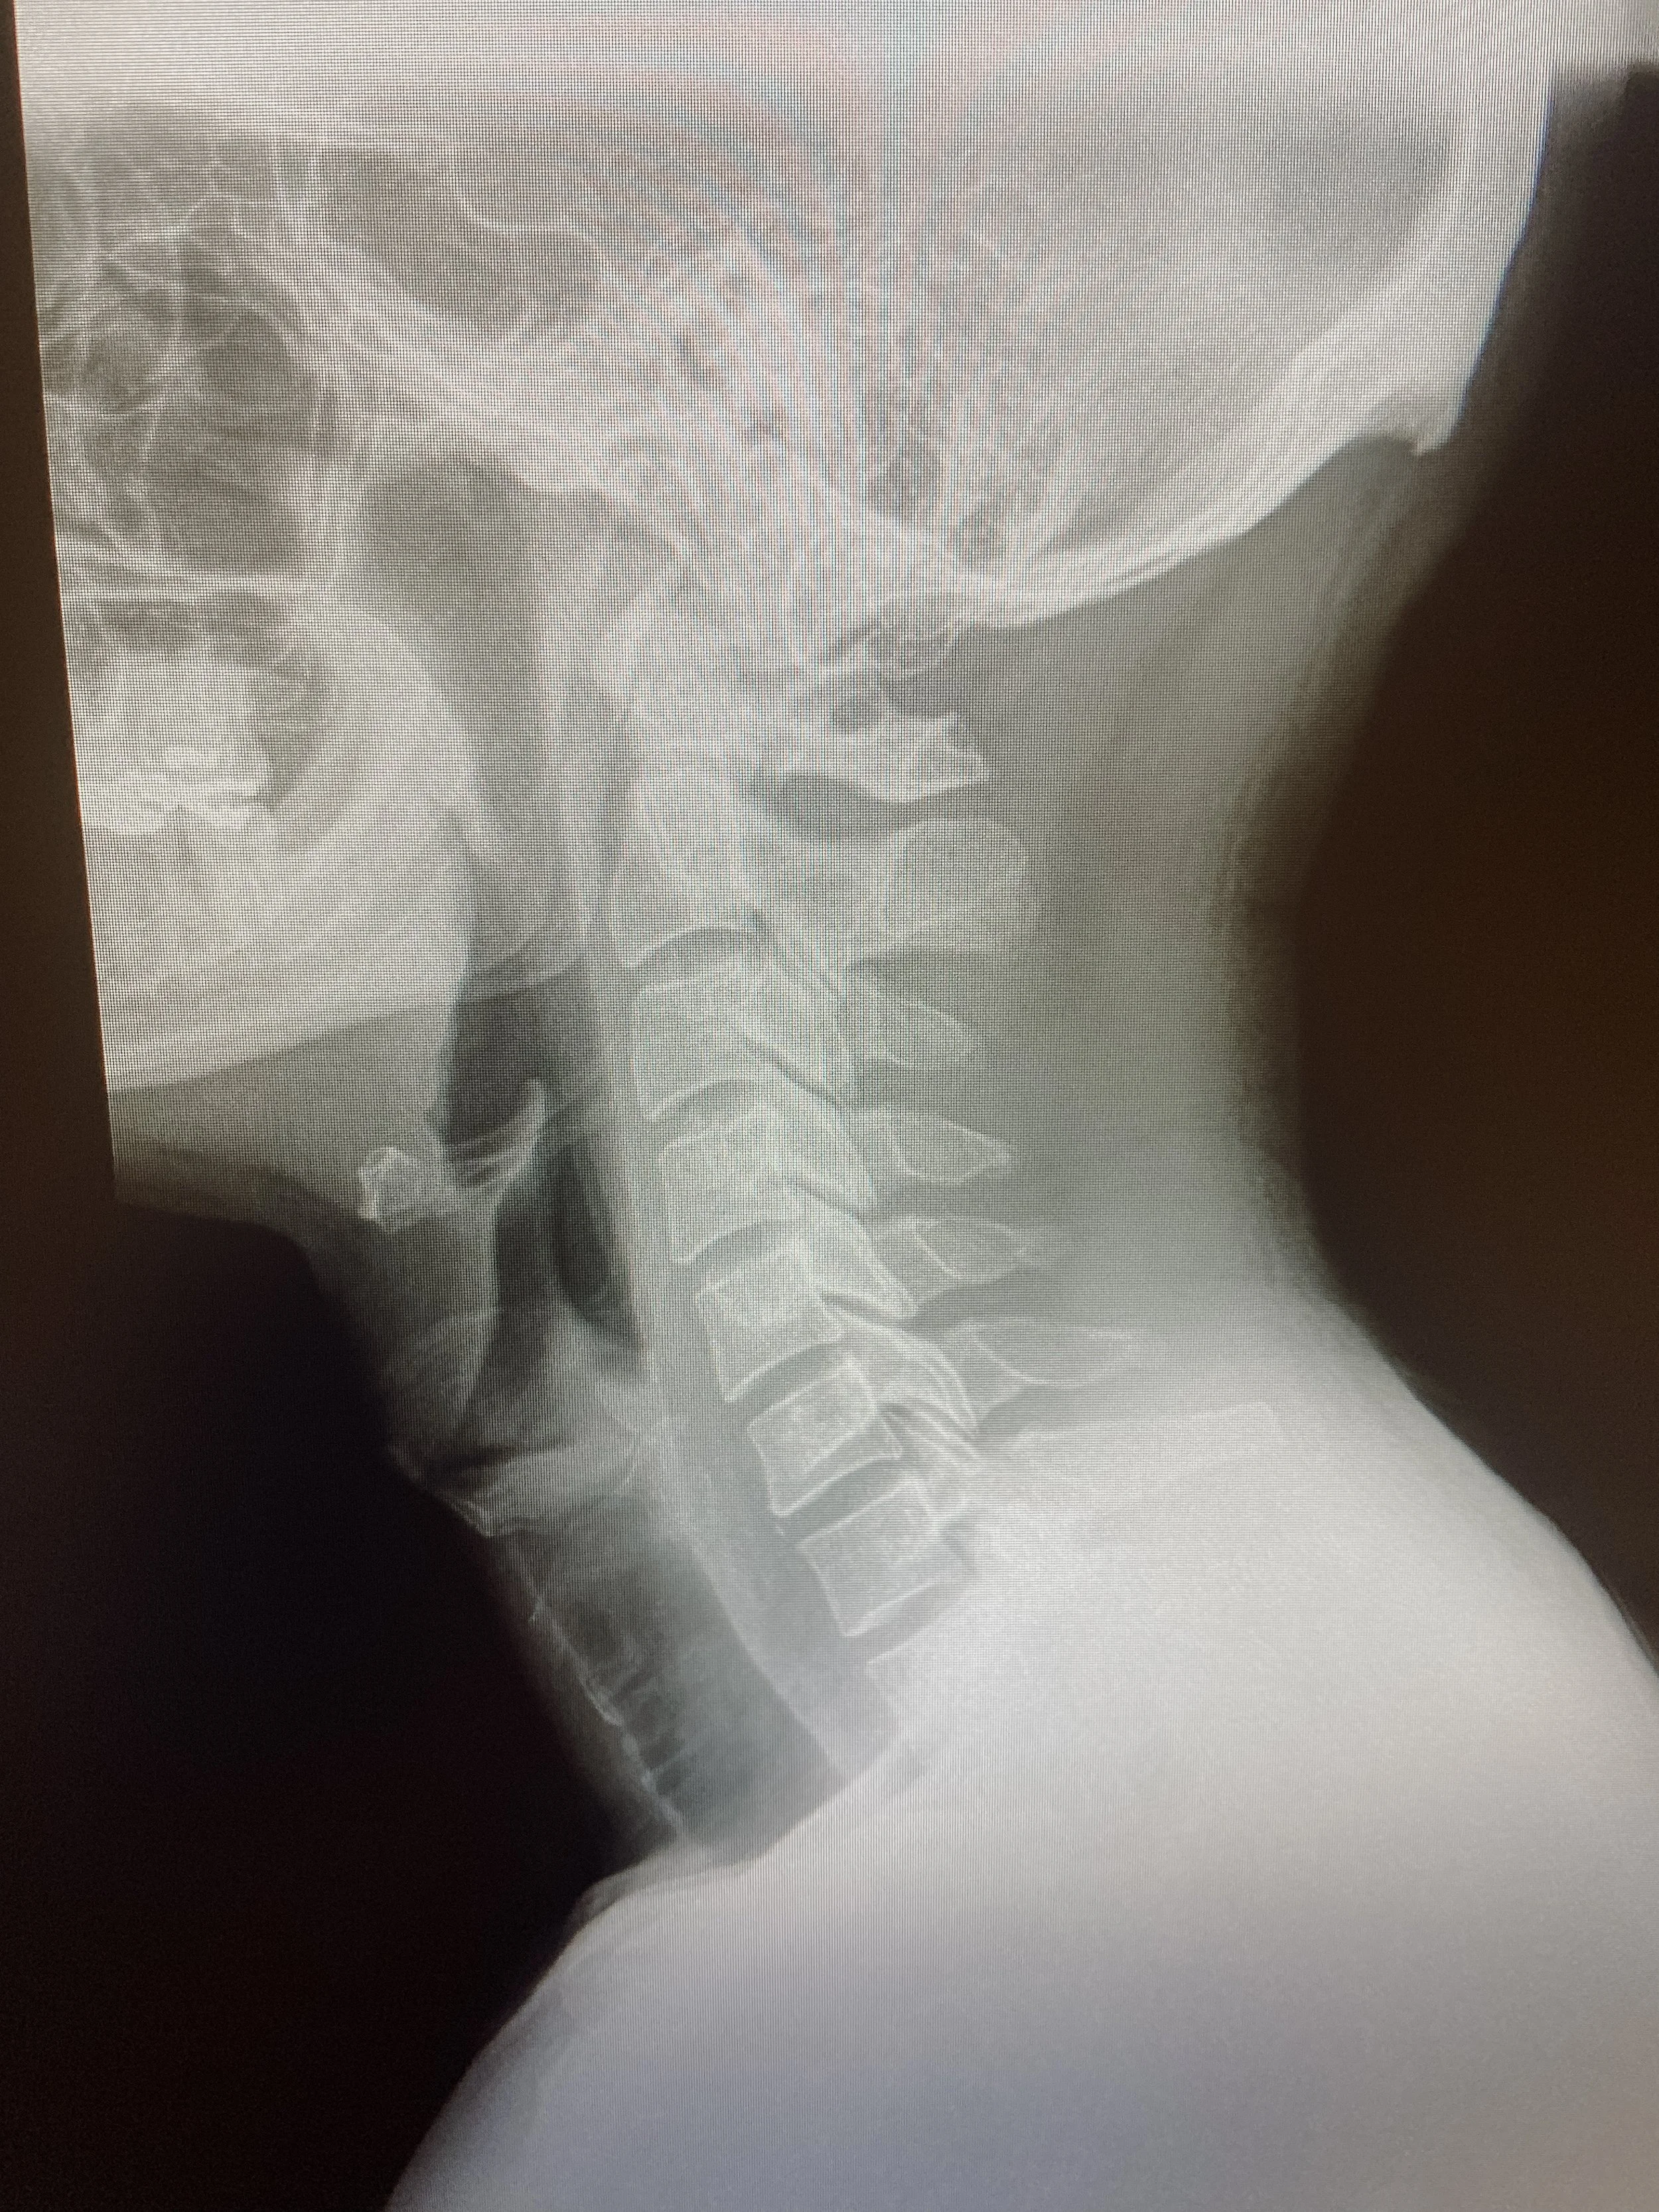

Radiology

𑁍 NO guessing at our clinic! X-ray is used to determine the cause of your condition.

𑁍 Rule out pathology that may need an outside referral.

𑁍 Reveals the extent of spinal degeneration, our bodies way of aging in the skeletal system.

𑁍 A great tool to have for comparison purposes.

𑁍 Allows the chiropractor to adjust more precisely, which gets better and faster results.

𑁍 Just like taking your blood pressure to check your cardiovascular health, an x-ray helps see how your spinal system is effecting your nervous system.